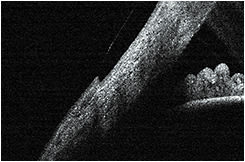

Typically, a scleral lens is divided into three fitting zones. First is a central zone, which vaults over the central cornea. Next is the midperipheral zone, which commonly is called the limbal clearance or transition zone. It is critical to avoid any limbal zone bearing in a successful scleral lens fit. Finally, there is the scleral landing zone, which lands on the bulbar conjunctival tissue (Figure 4). The scleral landing zone must not cause conjunctival compression (Figure 5), which will cause complications from impeding blood flow through the conjunctival vasculature. Conversely, edge lift off (Figure 6) also must be avoided or discomfort will occur.

Figure 5. Landing zone causing compression.